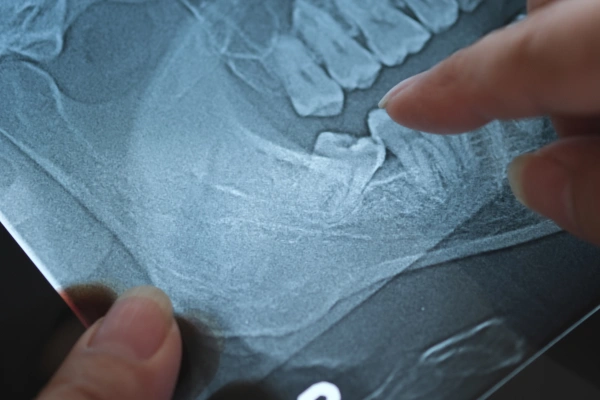

What Is a Wisdom Tooth Extraction & How Does It Work?

Wisdom tooth extraction is a controlled procedure to remove third molars that are decayed, painful, or impacted (stuck in gum or bone). Depending on the tooth’s position, the procedure may be simple, surgical or complex.

Digital X-rays, surgical planning, and precise removal techniques ensure minimal trauma and faster healing.

Impacted tooth on X-ray

To prevent nerve pressure, cysts, or jaw complications.

Digital X-Rays & Advanced Planning

Accurate imaging for safe, precise extractions.